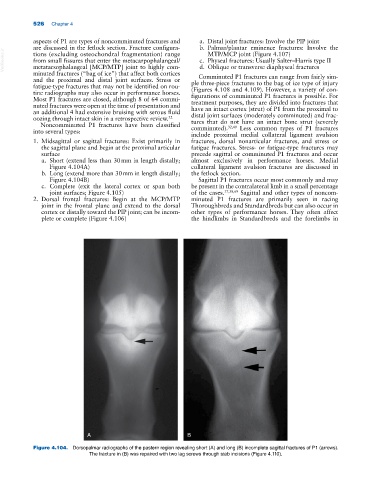

a. Short (extend less than 30 mm in length distally; almost exclusively in performance horses. Medial

Figure 4.104A) collateral ligament avulsion fractures are discussed in

b. Long (extend more than 30 mm in length distally; the fetlock section.

Figure 4.104B) Sagittal P1 fractures occur most commonly and may

Figure 4.104. Dorsopalmar radiographs of the pastern region revealing short (A) and long (B) incomplete sagittal fractures of P1 (arrows).

The fracture in (B) was repaired with two lag screws through stab incisions (Figure 4.110).